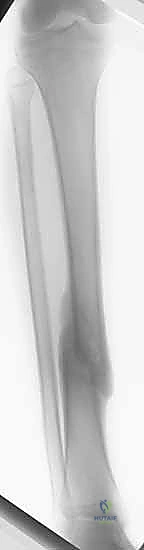

تُعتبر كسور عظم الساق (الظنبوب - Tibia) من أكثر إصابات العظام الطويلة شيوعًا وتعقيدًا في ممارسة جراحة العظام (Orthopedic Surgery) على مستوى العالم. يمثل عظم الساق الدعامة الأساسية التي تحمل الغالبية العظمى من وزن الجسم، وتنقل القوى الحركية والميكانيكية من الركبة إلى الكاحل والقدم أثناء المشي والجري والوقوف.

نظرًا لموقعه التشريحي السطحي جداً (حيث يقع تحت الجلد مباشرة في الجزء الأمامي من الساق دون غطاء عضلي كثيف يحميه)، فإنه يكون عرضة بشكل كبير للإصابات المباشرة وغير المباشرة. هذه الهشاشة التشريحية تجعل كسور الساق غالباً مصحوبة بإصابات في الأنسجة الرخوة المحيطة (الجلد، الأوعية الدموية، والأعصاب)، مما يزيد من تعقيد الحالة ويستوجب تدخلاً طبياً عالي الاحترافية.

يبدأ التشخيص بالفحص السريري الدقيق لتقييم حالة الجلد، النبض، والأعصاب. يتبع ذلك إجراء الأشعة السينية (X-rays) من زوايا متعددة لتحديد موقع وشكل الكسر بدقة. في حالات الكسور المعقدة أو التي تمتد إلى مفصل الركبة أو الكاحل، يطلب البروفيسور هطيف إجراء أشعة مقطعية (CT Scan) للحصول على صورة ثلاثية الأبعاد تساعد في التخطيط الجراحي الدقيق.